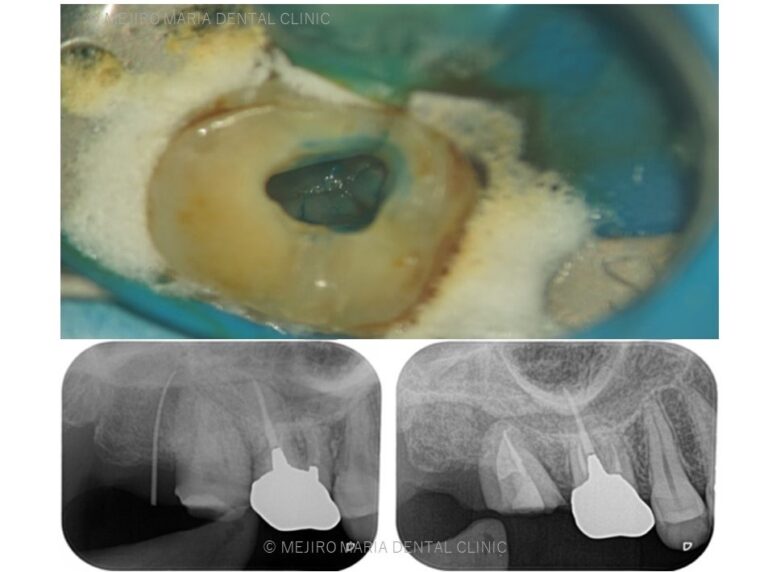

• 目白マリア歯科 親知らずの移植でインプラントを回避した症例レントゲン画像

【症例】親知らずを用いた歯牙移植でインプラントを回避